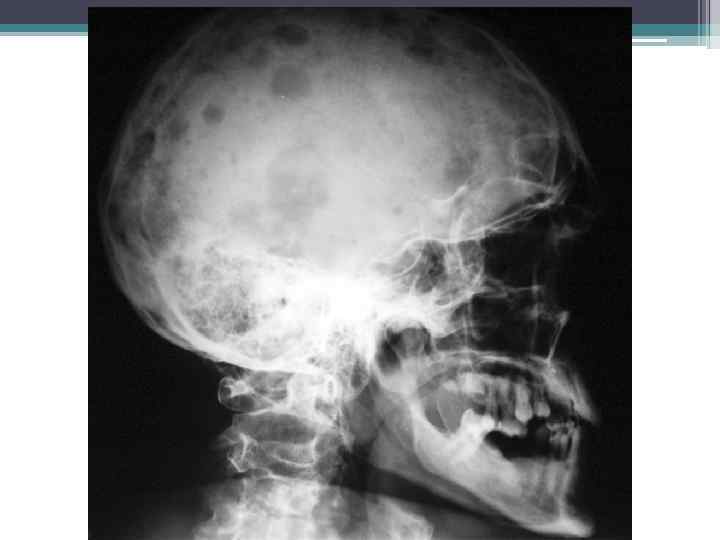

Рентгенограмма, демонстрирующая множественные очаги деструкции в костях, обусловленные миеломной болезнью. Патологический перелом локтевой кости.